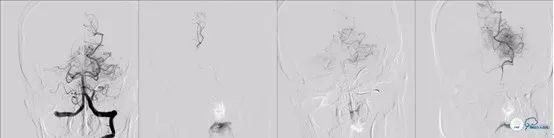

入院急查全脑血管造影术:可见基底动脉高密度征。

图2

图3

图4

图5

可见基底动脉尖端部血栓,呈次全闭塞状态,前向血流Mtici 2*级A**,无明显前循环向后循环代偿。